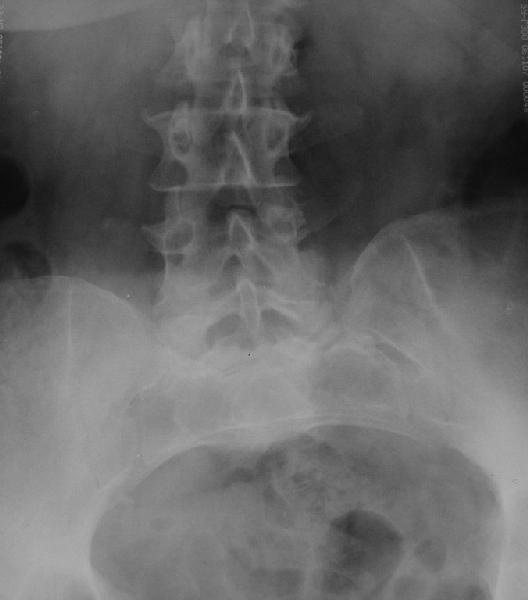

У больной 53 лет в последний год появились сильные боли в пояснице.

При обследовании выявлен анкилоз тазобедренного сустава в приведении. Видимо, в период пребывания в тяжелом состоянии появились гетеротопические оссификаты. За исключением того, что осталась одна почка, сейчас других медицинских проблем нет.

Пациентку в первую очередь беспокоят боли в спине, на отсутствие движений в суставе она вроде и не жалуется. Вопрос насчет тактики. Корсет и анальгетики вряд ли решение. Первый вариант - удаление оссификатов и эндпротезирование, второй - корригирующая остеотомия в проксимальном отделе с устранением порочного положения.

Крайне желательно выполнить МРТ поясничного отдела, так как на представленных рентгенограммах складывается впечатление о спондилолистезе L5,котрый наиболее вероятно и является причной болевого синдрома. Кроме того у болной имеется высокий риск гнойного поражения позвоночника. Только после МРТ можно планировать коррекцию вторичной деформации позвоночника.

Снимок поясничного отдела плохо просматривается на моем компе. Нет ли там спондилолистеза L5-S1?

Учитывая отсутствие жалоб со стороны тазобедренного сустава - оперативое лечение вряд ли принесет позитивный результат. На первый план выступает спондилолизный спондилолистез (вниматльно посмотрите снимки поясничного отдела)L5 позвонка. На наш взляд больному рекомндовано выполнить транспедикулярную коррекцию и фиксацию сегментов L4-S1 с установкой кейджа в L5-S1.